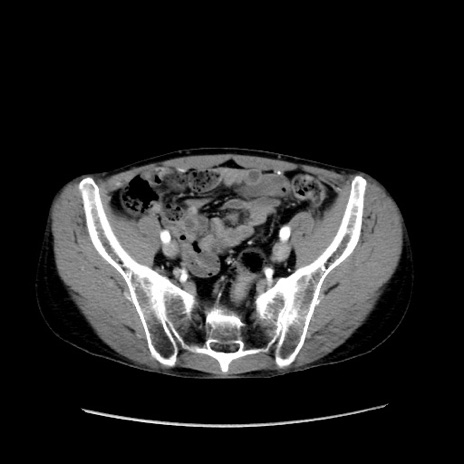

症例37(横断像)

【症例】40歳代 男性

【主訴】腹痛

【現病歴】4時間ほど前に電車に乗車中に臍部上より腹痛出現。徐々に増悪し起立困難となり、救急外来受診。生ものは数日食べていない。今朝お雑煮を食べた。

【身体所見】BT 36.8℃、BP 117/84mmHg、HR 91/min、SpO2 97%、苦悶様、腹部:臍上部広範囲圧痛あり、反跳痛±

【データ】WBC 8100、CRP 0.03